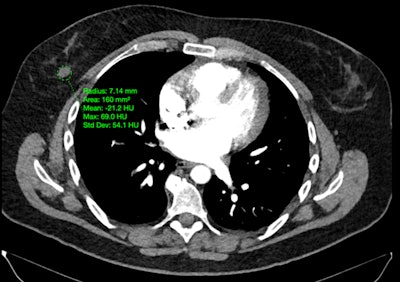

PET scans identify people at early risk for cognitive decline. Image from Guilherme Kolinger, MD, of Life Molecular Imaging in Germany, et al.

The study was conducted by scientists at Lantheus subsidiary Life Molecular Imaging, with the image demonstrating how quantitative analysis can reveal additional insights beyond standard visual assessment in amyloid PET.

“To identify the region highlighted in red, an amyloid-negative population (at baseline) with subjective cognitive decline was assessed with a voxel-based analysis using standardized uptake value ratios (SUVRs). Then, the baseline SUVR images of amyloid accumulators versus nonaccumulators were compared. Amyloid accumulation status was defined using the Centiloid method and with a five-year follow-up,” lead author Guilherme Kolinger, MD, explained to AuntMinnie.

The results showed that accumulators exhibited higher baseline SUVR in the red-marked region, which corresponds to part of the precuneus, a brain area known to play a role in early Alzheimer’s disease. This region overlaps with the Centiloid target region (shown in blue), underscoring the potential of this approach to enhance preclinical Alzheimer’s disease assessment, Kolinger added.